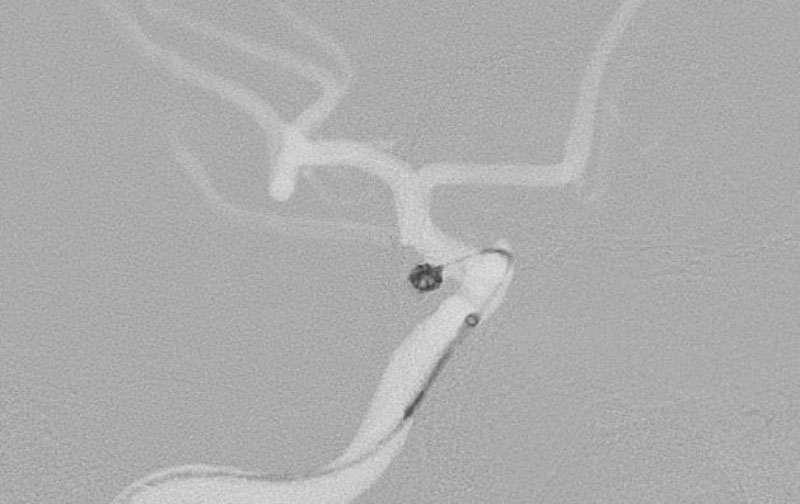

'26年4月

左後下小脳動脈瘤

80代

大阪府の病院

No.1631 手術前

No.1631 手術中

No.1631 手術後